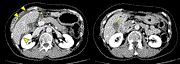

Laparoscopic sigmoidectomy for sigmoid colon cancer with left-sided inferior vena cava and persistent descending mesocolon

Masayo Kawakami and others

Journal of Surgical Case Reports, Volume 2020, Issue 7, July 2020, rjaa259, https://doi.org/10.1093/jscr/rjaa259